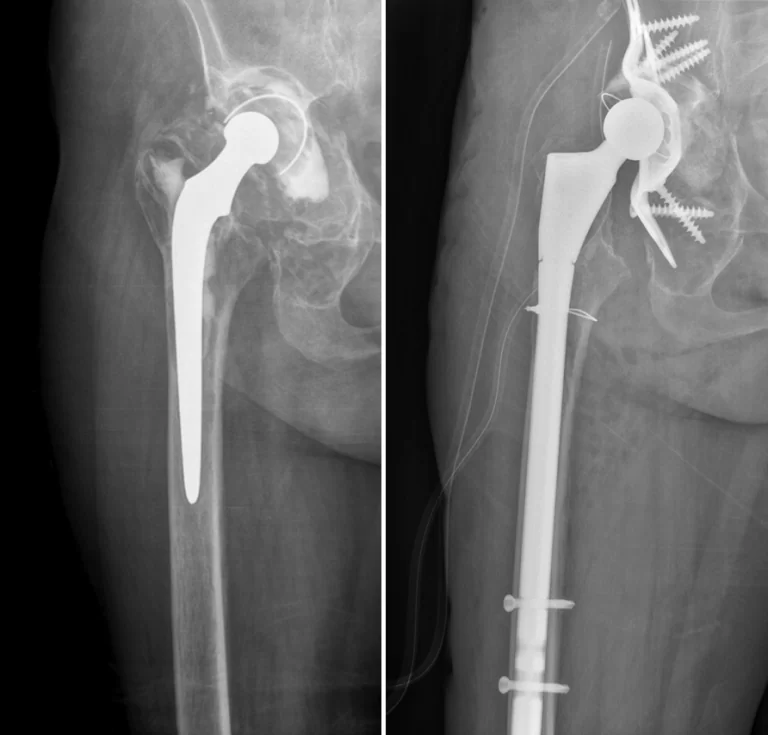

periprotetikus törések a különböző beültetett nagyízületi protézisek körüli töréseket jelentik. Mivel egyre több beteg rendelkezik valamilyen nagyízületi implantátummal, ezért az ilyen jellegű törések száma jelentősen emelkedik az elmúlt években. Ezen betegek ellátása sok esetben kihívás a kezelőorvos számára, mivel komplex ortopédiai és traumatológiai gondolkodást igényel. Nem elégséges a csont törését kezelni, gondolni kell a beültetett protézis stabilitására is. Sok esetben ezen törések már kilazult protézisek melletti kikopott, meggyengült csontállomány miatt következnek be.

A reviziós műtétek a korábbi hegszövet oldását, az érintett protézis-komponensek eltávolítását, a cement kivésését és eltávolítását, majd új protézis beültetését jelenti. A revíziós műtétek a legtöbb esetben jóval nagyobb műtéti feltárást, nagyobb vérzést, hosszabb műtétet, nagyobb és bonyolultabb műtétet jelentenek orvos és beteg számára egyaránt. A cement kivétele után a meggyengült csontállományt kell előkészíteni az új implantátum stabil befogadására. Térdprotézis esetén ehhez szükség lehet csontpótlásra és speciális augmentációval ellátható száras protézisek alkalmazására. Csípőprotézis esetén a medencecsontban kell kialakítani az új vápa befogadására alkalmas területet.

Gyakran szükséges csontpótlás alkalmazása, csavarozás, vápakosár beültetése a végleges vápakomponens beültetése előtt.

A csípőprotézis szárának befogadására gyakran alkalmatlan a combcsont korábbi csípőízülethez közelebb eső felső része, így általánosságban hosszabb, akár reteszelt szárakat szükséges beültetni, csontpótlással, lemezeléssel és/vagy húzóhurok (cerclage) alkalmazásával együtt. Általánosságban elmondható, hogy revíziók során cement nélküli rendszerek alkalmazása van előtérben.